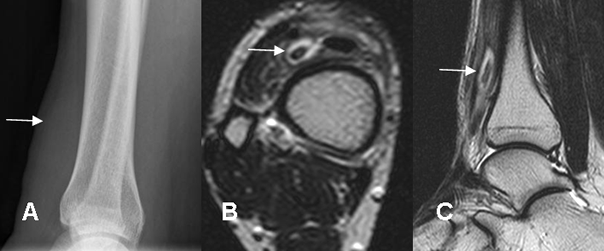

Fig 32. Cuerpo extraño.

A: Rx lateral. Prominencia de los tejidos blandos de la pierna, sin alteraciones óseas.

B: RM axial y C: RM sagital en T2. Se identifica imagen ovalada e hipointensa, rodeada por líquido. El paciente tenía antecedente de trauma y se extrajo un trozo de madera.